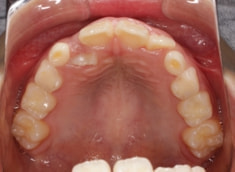

治療前